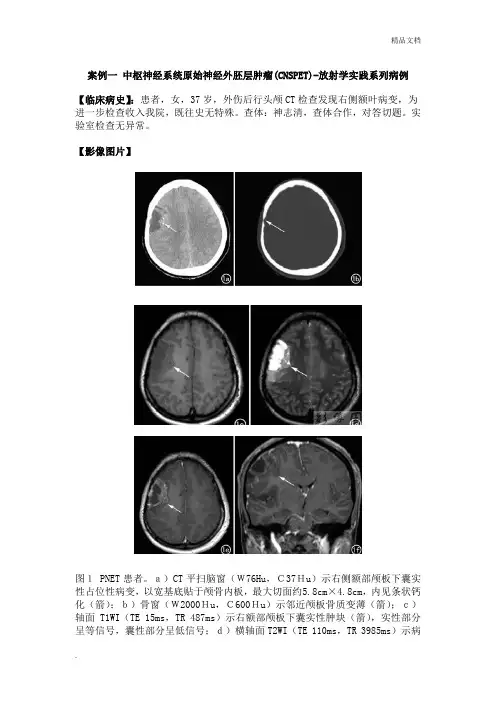

案例一中枢神经系统原始神经外胚层肿瘤(CNSPET)-放射学实践系列病例【临床病史】:患者,女,37岁,外伤后行头颅CT检查发现右侧额叶病变,为进一步检查收入我院,既往史无特殊。

查体:神志清,查体合作,对答切题。

实验室检查无异常。

【影像图片】图1 PNET患者。

a)CT平扫脑窗(W76Hu,C37Hu)示右侧额部颅板下囊实性占位性病变,以宽基底贴于颅骨内板,最大切面约5.8cm×4.8cm,内见条状钙化(箭);b)骨窗(W2000Hu,C600Hu)示邻近颅板骨质变薄(箭);c)轴面T1WI(TE 15ms,TR 487ms)示右额部颅板下囊实性肿块(箭),实性部分呈等信号,囊性部分呈低信号;d)横轴面T2WI(TE 110ms,TR 3985ms)示病灶实性部分呈等、偏高信号,囊性部分呈高信号,灶周可见轻度水肿(箭);e)横轴面T1WI增强扫描示病灶呈不规则厚壁环形强化(箭),囊性部分无强化;f)冠状面T1WI增强扫描示病灶呈不规则环形强化,囊性部分无强化(箭);g)病理图示肿瘤由致密的小圆细胞构成,细胞核深染,核仁不明显,细胞密集。

【影像表现】:CT检查:右侧额部颅板下囊实性占位性病变,最大切面约5.8cmX4.8cm,内见条状钙化,病灶以宽基底贴于颅骨内板并邻近颅板骨质变薄,侧脑室受压,中线结构轻度左移(图a-b)。

MRI检查:右额部颅板下囊实性肿块,实性部分呈等T1、长T2信号,灶周轻度水肿,增强扫描呈不规则厚壁环形强化(图c~f)。

【手术所见】:右额下回后方一实性肿物,其基底为脑表面,大小约5cmX5cm,质软,色暗红,血供丰富,无包膜,见肿瘤突出脑皮层表面并向四周硬膜下腔延伸,肿瘤侵入脑内达3cm,与正常脑组织分界不清。

【病理结果】:考虑为中枢神经系统原始神经外胚层肿瘤(PNET)(图1g)。

【讨论】:原始神经外胚层肿瘤(PNET)是一类由原始神经上皮细胞衍化而来的高度恶性肿瘤,侵袭性强、预后差。